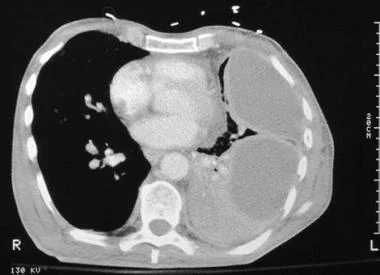

2. 胸部CT扫描

胸部CT增强扫描可增强胸膜表面,有助于描绘积液位置。

图3 胸部CT扫描显示左侧包裹性胸腔积液和脏层胸膜对比增强,表明病因可能是脓胸。